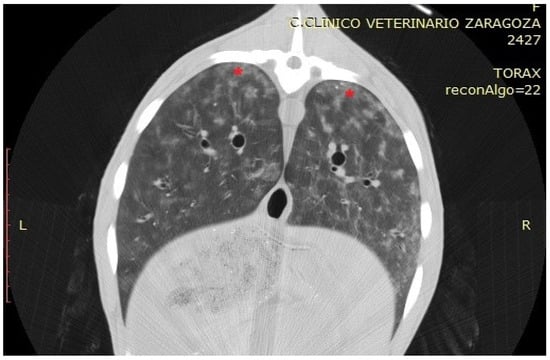

3.3.1. Interstitial Pneumonia (SRLV)

| SRLV | Diffuse, entire lung parenchyma | 800 to −400 HU | Severity-dependent: mild (−700 to −800 HU), moderate (−550 to −700 HU), severe (−400 to −550 HU); reflects cellular infiltration |